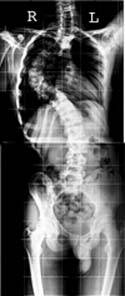

What are Full Length Digital

X-rays?

Full-length radiographs are important radiographs

in orthopedics, where x-rays of the whole spine or

the entire lower limbs are obtained. These are mainly

indicated for measurements of length and angles and

important prior to some types of surgeries.

Why are Full Length X-rays such a big deal?

Traditionally, it has been difficult to obtain full-length

radiographs in our part of the world on a regular

basis - many of us have tried local, ingenious methods

of getting those three or two radiographs and taping

them together.With the digital x-ray technology, we

are now able to "stitch" multiple radiographs

to obtain full-length images, which are then printed

on one film. Two representative examples are given

alongside. |